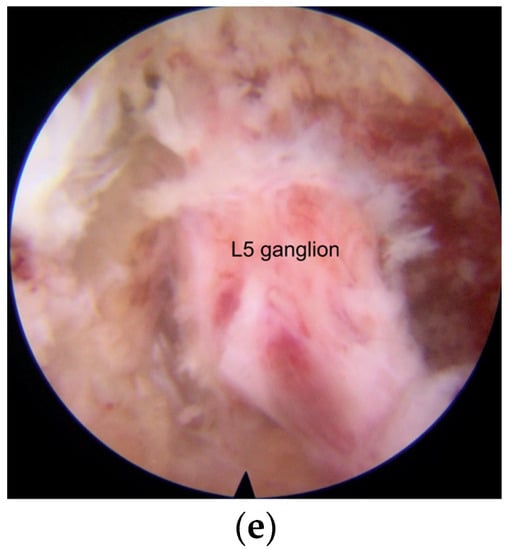

2.3. Surgical Procedures

- Under the endoscopic view, the structure of the foramen can be seen more clearly. Smaller operating instruments used in endoscopic operation can avoid irritating DRG.

- The modified interlaminar approach we used can show an almost parallel trajectory to the L5 nerve root in the foramen and provide excellent visualization of the nerve root all along its course without the need for significant retraction. This technique was called “no touch decompression” [36], as FS can be treated without more retraction of DRG compared with that via transforaminal approach, especially in complicated cases and L5-S1 cases with anatomical limitations [37].